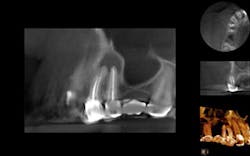

Nonsurgical endodontic retreatment with the aid of cone beam (CBCT) imaging

Endodontic therapy under current treatment protocol shows long-term clinical success rates of 86% to 92%. Even with the high clinical success rate of initial endodontic treatment, it’s obvious to see this leaves clinicians with a 14% incidence (on the high side) of encountering post-treatment disease. Dr. Brian McCormack presents a case that was treated with the aid of CBCT imaging and a surgical operating microscope. Click here to read the article.